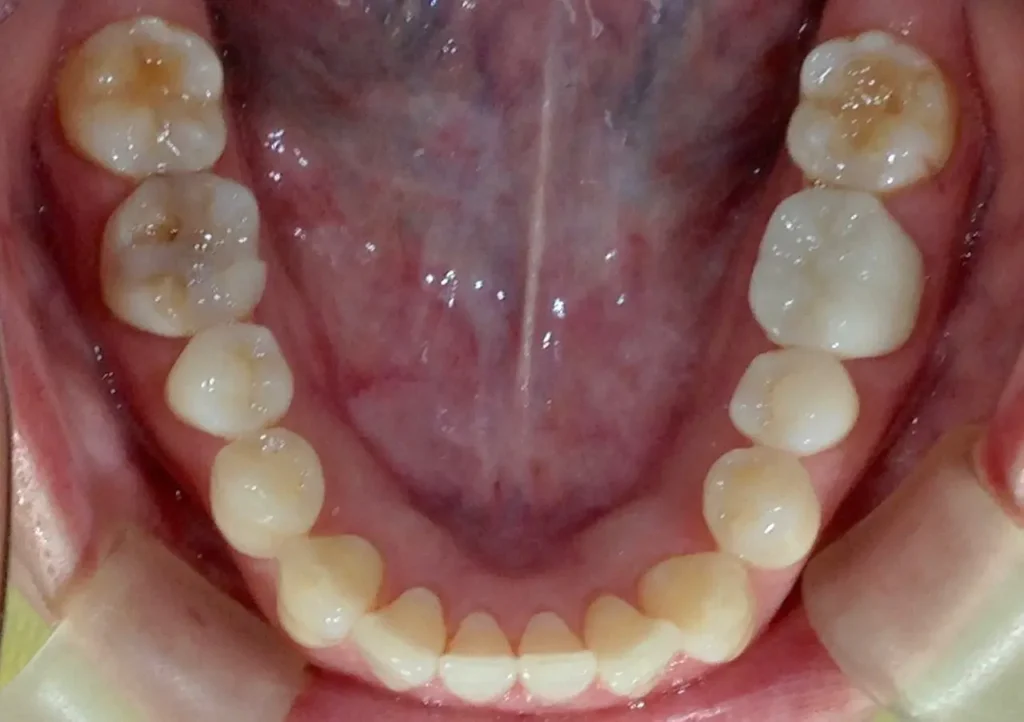

口腔内写真

向かって奥から2番目審美性も機能も維持されています